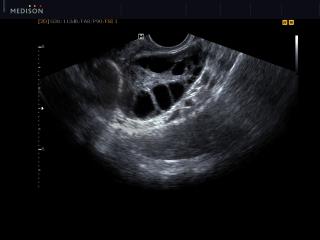

Atlas of ultrasound images - gynecology

In the section "Gynecology" of atlas the results of ultrasound examinations of female maladies are represented. Here you can see images of uterus and ovaries, fallopian tubes and urinary bladder, the sonograms of ectopic pregnancy, endometrial polyp, myoma, cystic lesion, bicornuate uterus, etc.